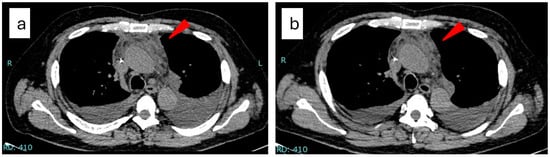

- Kiguchi, T.; Sato, C.; Takai, K.; Nakai, Y.; Kaneko, Y.; Matsuki, M. CT findings in 11 patients with TAFRO syndrome: A variant of multicentric Castleman’s disease. Clin. Radiol. 2017, 72, 905.e1–905.e5. [Google Scholar] [CrossRef]